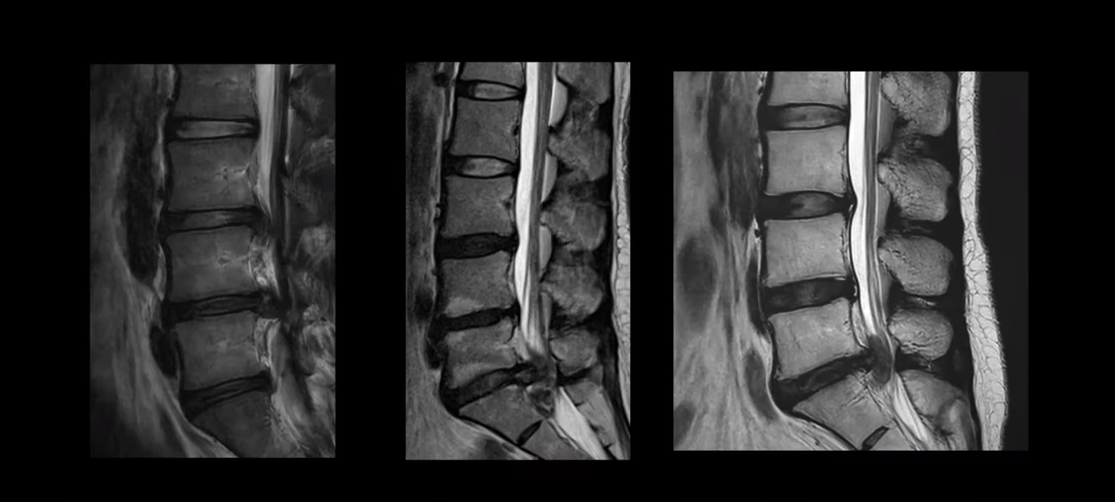

여기 MRI를 보시면 디스크 파열이 엄청나게 심한 분들입니다. 보시다시피 파열이 너무 심해서 이런 분들이 정형외과나 신경외과 가시면 거의 다 바로 수술하라는 얘기를 듣습니다. 그런데 이런 심한 파열일수록 오히려 치료가 더 잘 될 가능성이 매우 높다고 말씀 드리는 겁니다. 이분들 비수술 치료후기는 아래 영상을 참고하시길 바랍니다.

디스크 파열이 심한 환자들일수록 비수술치료가 잘 되는 이유 첫 번째, 파열이 심하면 심할수록 밀려나온 수핵이 흡수가 더 잘 됩니다. 심하게 파열되어 밀려나온 디스크 수핵은 우리 몸에서 이물질로 인식하기 때문에 우리 몸의 면역시스템이 이를 제거하기 위한 작업, 즉 염증반응을 시작하게 됩니다. 즉 우리 몸의 면역시스템이 밀려나온 디스크 수핵을 녹여서 없애버리는 겁니다. 그래서 디스크 파열이 심하면 심할수록 오히려 흡수가 더 잘 되는 겁니다. 이에 대한 자세한 내용은 아래 영상을 참고하시길 바랍니다.